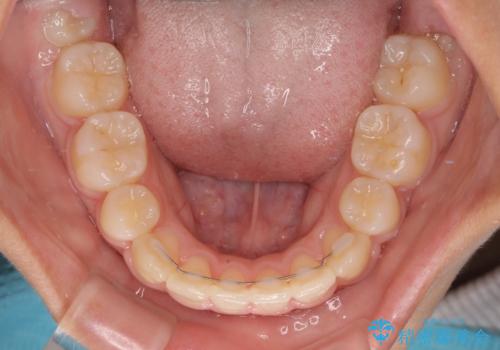

急速拡大後、歯列はきれいに並んだのですが、口元が出っ歯になってしまったため、速やかに抜歯を行い、治療期間がいたずらに遅延することのないようにしました。